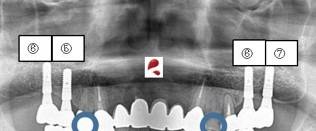

インプラントで「後悔」する人に共通する3つの理由

「絶対だめ」という極端な意見もありますが、実際には正しく行えば「生活の質(QOL)」を劇的に上げる治療であることも事実です。